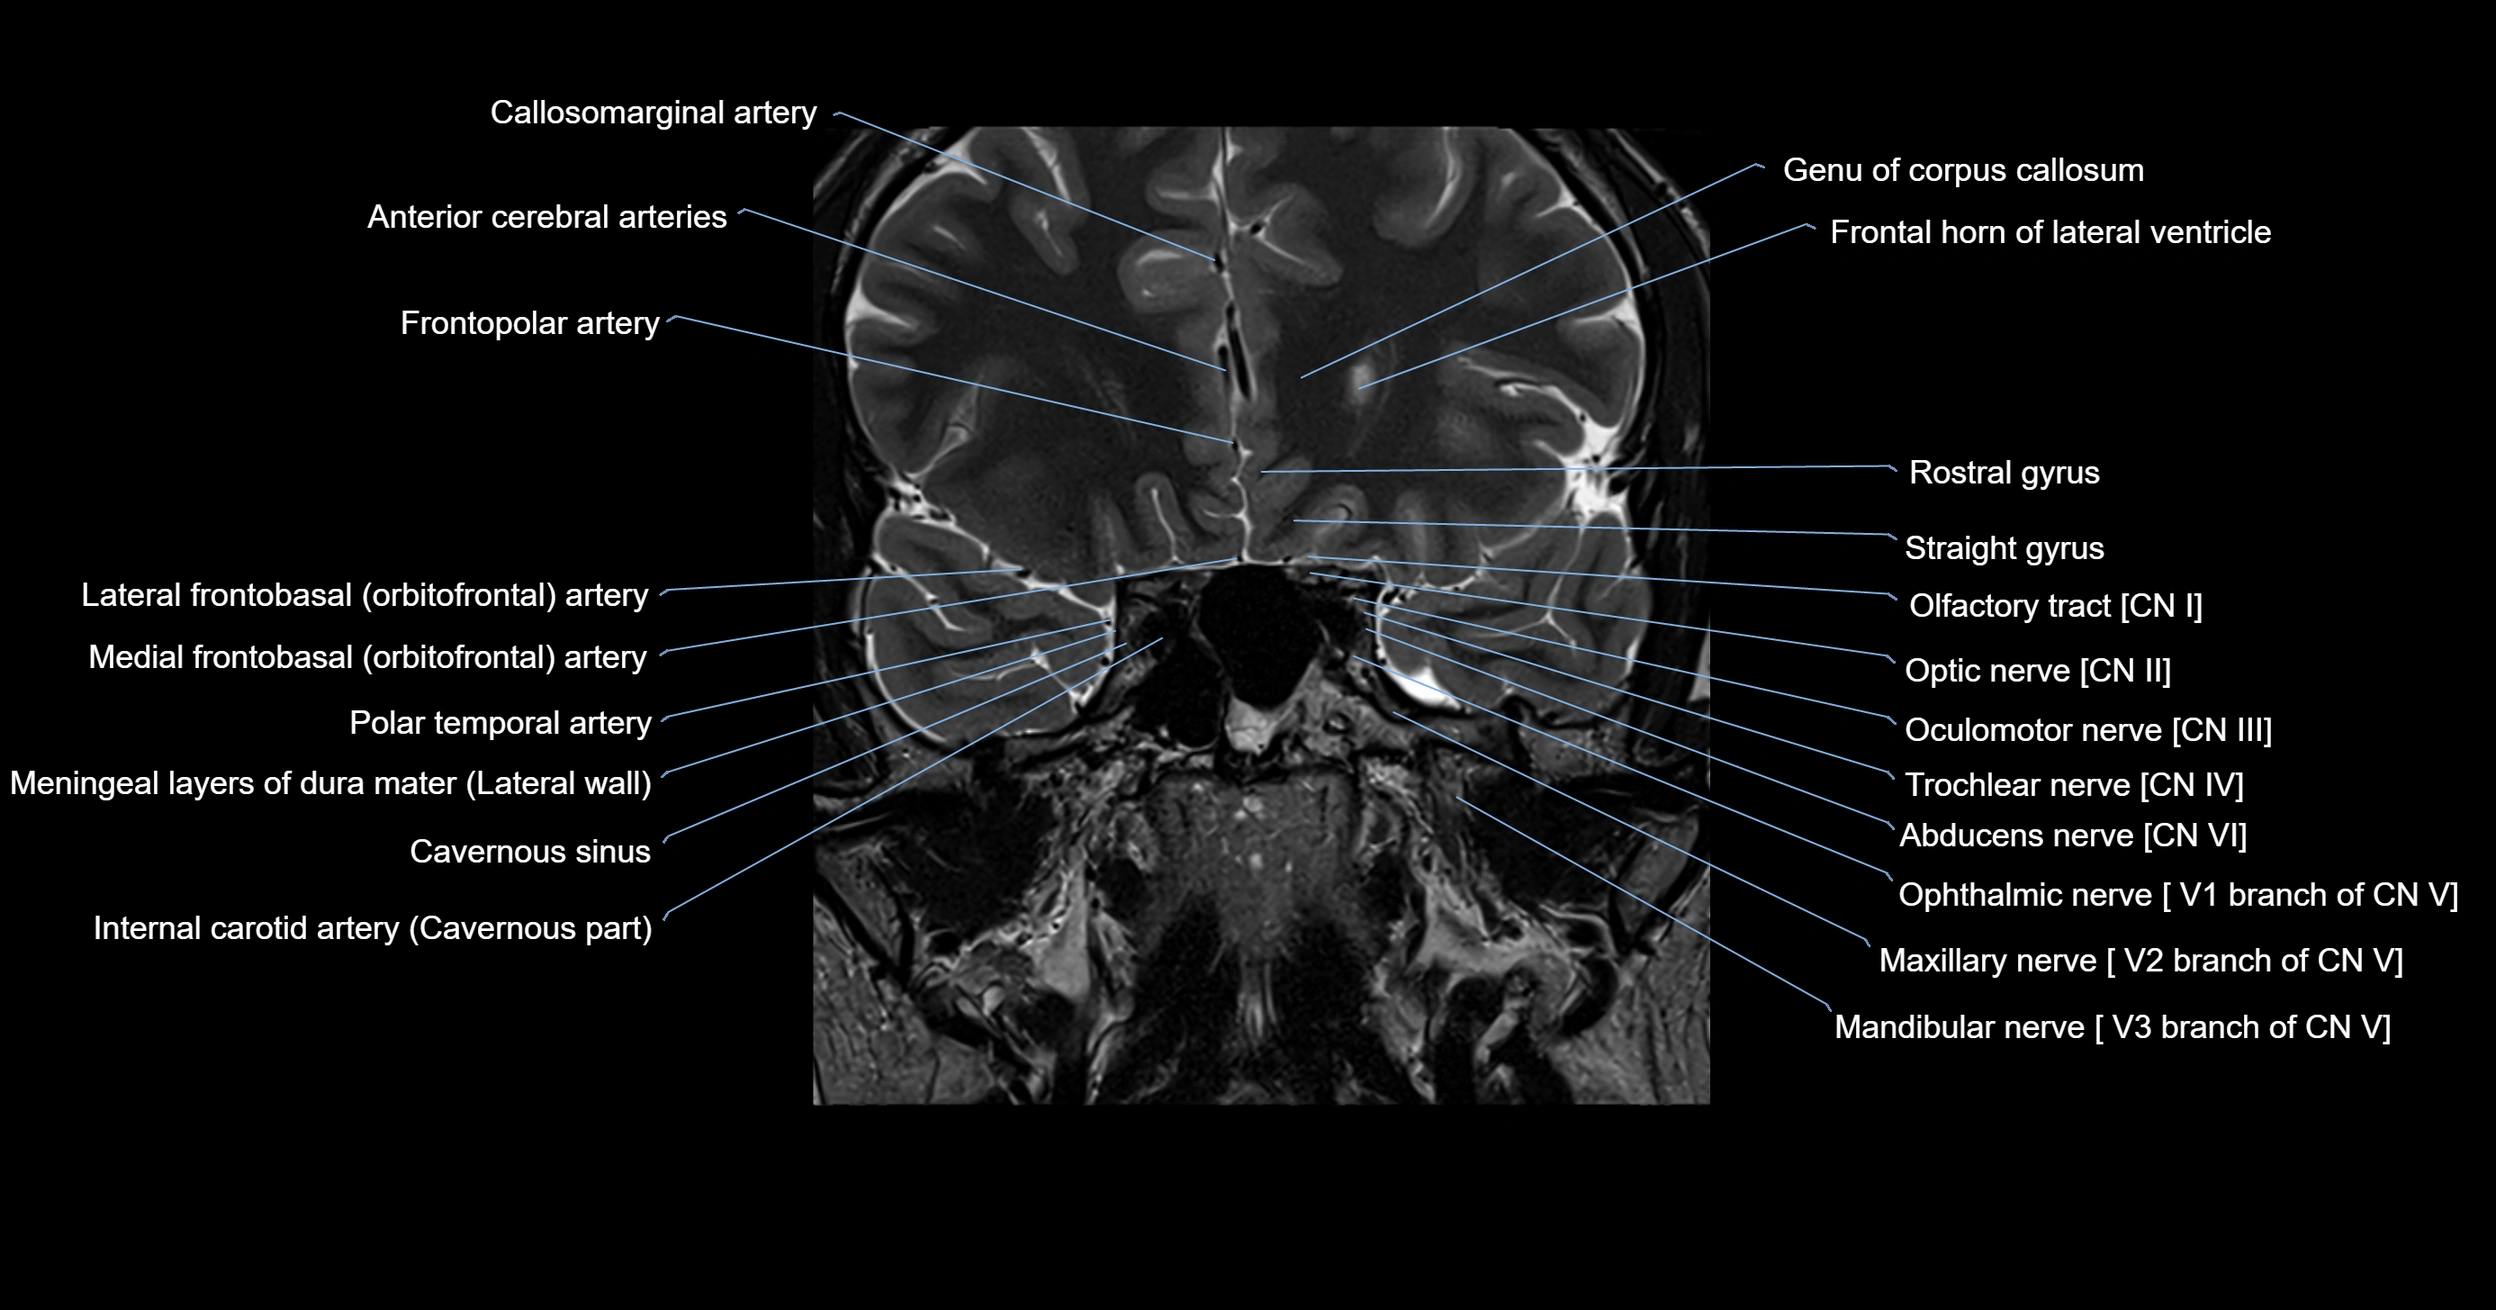

MRI images